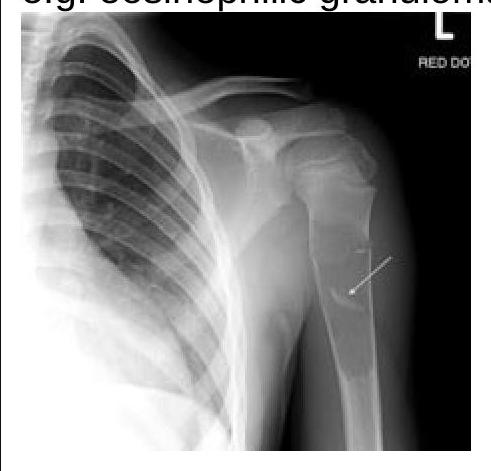

What type of lesions in the skull bones can be identified on this X-ray?

Explanation: ***Paget's disease*** - An X-ray of the skull in Paget's disease typically shows **thickening of the skull vault** and areas of both **osteolysis** and **osteosclerosis**, leading to a characteristic "cotton wool" appearance. - The disease involves abnormal bone remodeling, leading to enlarged and weakened bones susceptible to deformity and fracture. *Multiple myeloma* - On a skull X-ray, multiple myeloma usually presents as multiple, sharply-defined, **"punched-out" lytic lesions** without a sclerotic border. - These lesions reflect areas where malignant plasma cells have destroyed bone, which is distinct from the mixed lytic and sclerotic changes of Paget's disease. *Osteosarcoma* - Osteosarcoma is a **primary bone malignancy** that typically presents as a solitary lesion with a mixture of lytic and sclerotic areas, often with a **sunburst or Codman's triangle** periosteal reaction. - It most commonly affects long bones in younger individuals and is a much less common presentation in the skull compared to other bone conditions. *Osteomyelitis* - Osteomyelitis is an **infection of the bone** that would appear on an X-ray as areas of bone destruction (lysis) and new bone formation (sclerosis), often with **sequestrum** (dead bone) and **involucrum** (new bone formation around the infection). - While it can affect the skull, its imaging features would typically be localized signs of infection rather than the widespread, generalized changes seen in Paget's disease.